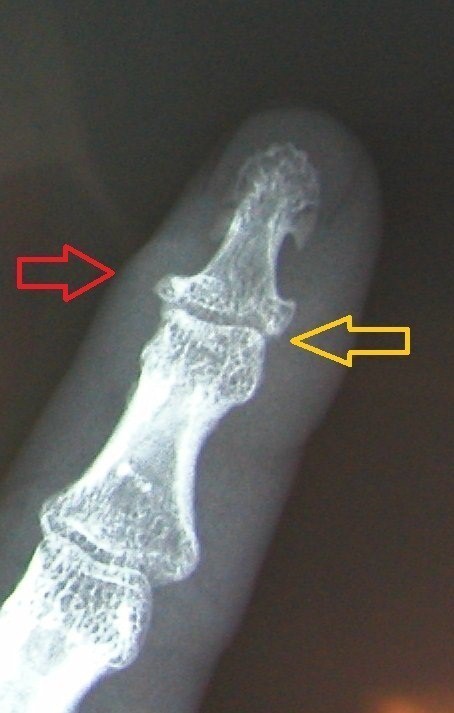

Finger-end joint stiffening and middle joint replacement in rheumatoid patients.

Left: Red Arrow: Horn-like deposits as an sign of osteoarthritis, yellow arrow: complete destruction of the joints, with inflammation and pain at rest and at work.